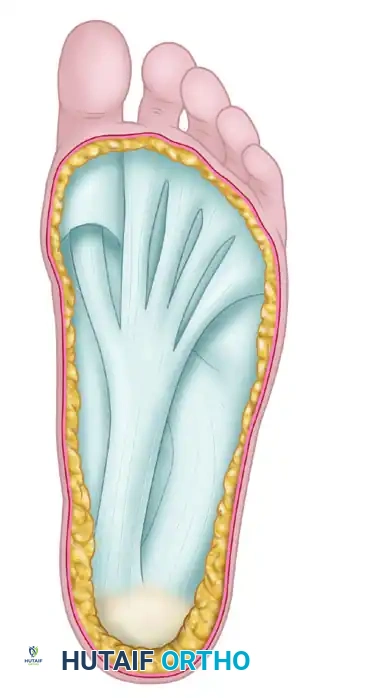

Anatomical representation of the plantar aponeurosis. The dense central and medial bands are the primary targets for release in the cavovarus foot.